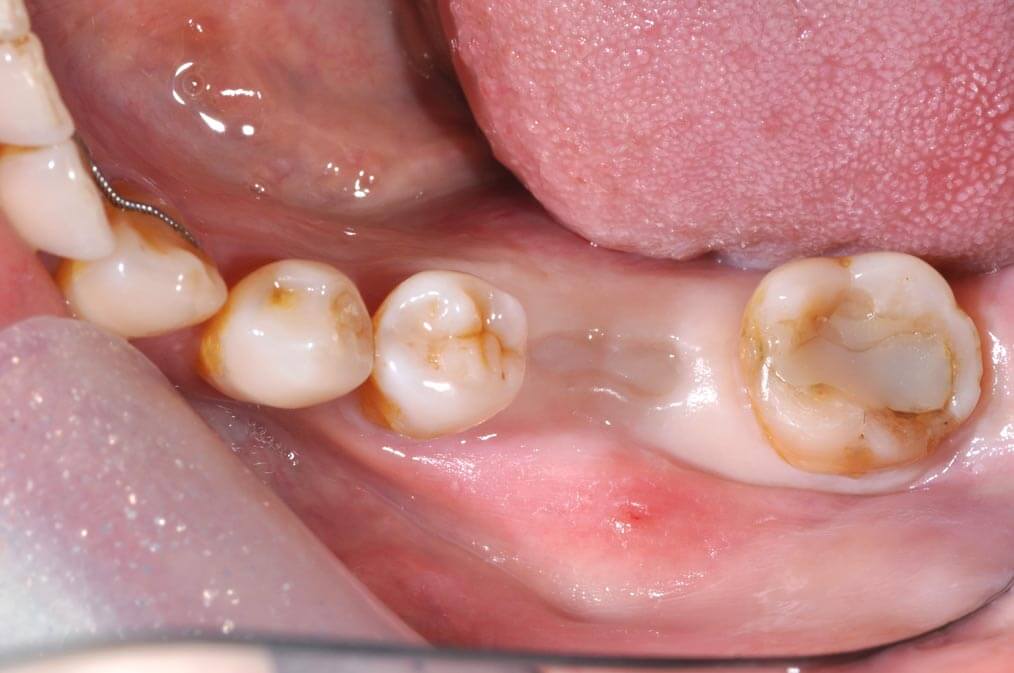

植牙前

臨時假牙/牙齦塑形器

常常覺得植牙完後會卡食物嗎? 現在用牙齦塑形器就可以避免了。

在安裝正式植牙假牙前,會先按照電腦規劃的結果設計,製作臨時假牙/牙齦塑形器,用來塑形牙肉使其恢復至正常的牙縫型態,避免日後發生卡牙縫的問題。